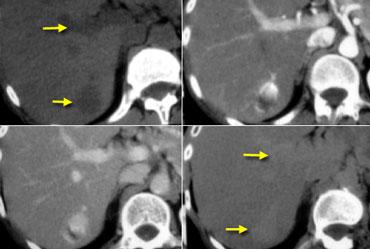

U máu gan trên CT không tiêm thuốc, thì động mạch muộn, thì tĩnh mạch cửa muộn và thì cân bằng. Lưu ý tỷ trọng của u máu tương đương với hồ máu trong tất cả các thì (mũi tên).

Hồ máu và U máu gan

Thông thường khi đánh giá các tổn thương ngấm thuốc, tỷ trọng của tổn thương luôn được so sánh với tỷ trọng của nhu mô gan.

Tuy nhiên, đối với u máu gan, không nên so sánh tỷ trọng của tổn thương với gan mà phải so sánh với hồ máu.

Điều này có nghĩa là các vùng ngấm thuốc trong u máu phải tương đương với tỷ trọng của các mạch máu tương ứng (hồ máu) ở mọi thời điểm.

Vì vậy, trong thì động mạch, các phần ngấm thuốc của tổn thương phải có giá trị tỷ trọng gần bằng với động mạch chủ đang ngấm thuốc, trong khi ở thì tĩnh mạch cửa phải tương đương với sự ngấm thuốc của tĩnh mạch cửa.

Nếu tỷ trọng không tương đương với hồ máu trong tất cả các thì tiêm thuốc, hãy loại bỏ chẩn đoán u máu gan.

Hình bên trái là một u máu gan điển hình.

Lưu ý rằng trên CT không tiêm thuốc, tỷ trọng của khối u tương đương với tỷ trọng của các mạch máu.

Trong thì động mạch, tỷ trọng tương đương với hồ máu và gần bằng với động mạch chủ.

Trong thì tĩnh mạch cửa, tỷ trọng tương đương với tĩnh mạch cửa.

Trong thì cân bằng, tỷ trọng ngấm thuốc tương đương với các mạch máu.

Cuối cùng tổn thương sẽ trở nên đồng tỷ trọng với gan, nhưng chỉ vì các mạch máu cũng trở nên đồng tỷ trọng với gan.

Điều này không liên quan đến tỷ trọng của bản thân nhu mô gan.

Vì vậy, hãy nghĩ đến hồ máu thay vì gan khi nghĩ đến u máu gan.